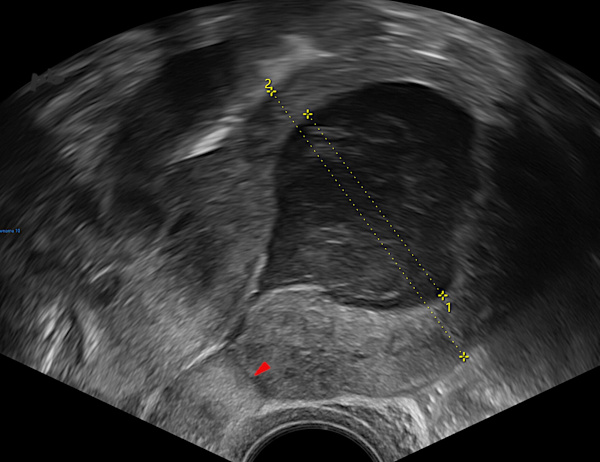

1 – Hématométrie

Rétention hématique après césarienne.

La cavité utérine (croix 1) est élargie et remplie de sang hypoéchogène.

Cicatrice de césarienne (►)